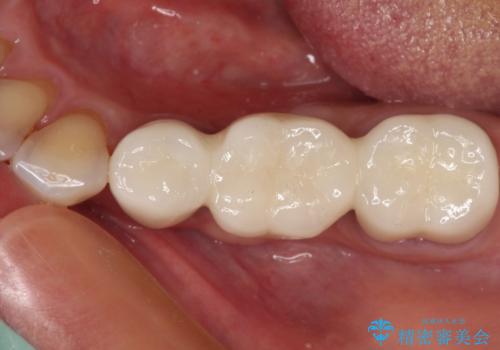

割れてしまった奥歯をインプラントで 気になる銀歯もセラミッククラウンで審美的に

下顎の部分矯正を行ってから奥歯の補綴治療とインプラント治療

担当医 藤巻太一朗